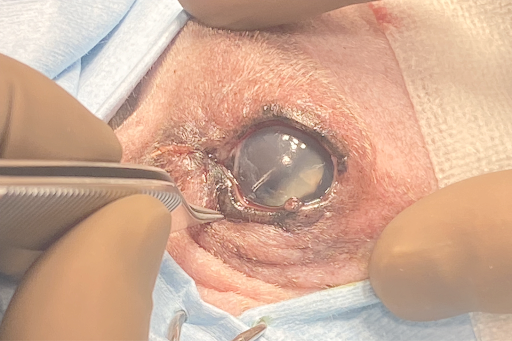

こちらが手術時の目の様子です。

犬の目には白内障があり、腫瘤により水晶体が押されている様子も確認されました。